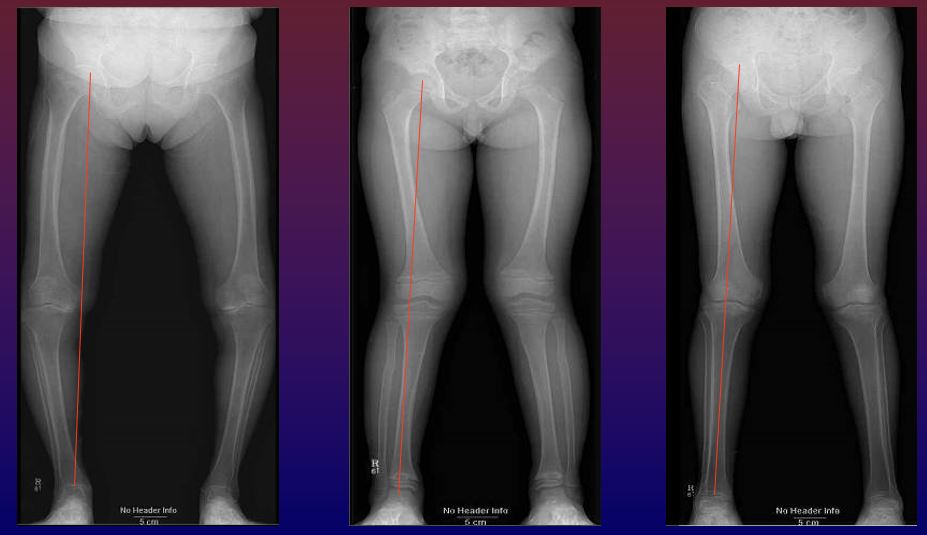

Femur head, Knee, Ankle을 연결하는 선과 ASIS에서 Tibia Tubercle을 연결하는 선이 이루는 각을 조사하여 Valgus와 Varus의 정도를 파악하는 것입니다. Hip joint부터 Knee, Ankle joint까지 모두 포함되어야 올바른 검사입니다. 그리고 모든 Joint가 true AP가 되어야 합니다. 몸이 좌우로 기울어짐이 없어야 합니다.

LONG BONE 검사는 슬관절의 퇴행성 변화, 외상, 기타 여러 가지 이유로 인하여 슬관절에 변형이 생겨 하퇴골 전체의 생체역학적 축(Static Aligments)에 이상이 있다는 판단이 들면 진행합니다.

LONG BONE 검사의 목적은 Mechanical Axis와 Anatomical Axis의 역학적 관계를 조사하고, Valgus와 Varus의 정도를 파악하여 수술계획의 바탕을 제공함에 있습니다.

- 비만증, 내반슬, 외반슬 등 기계적 부하축의 이상